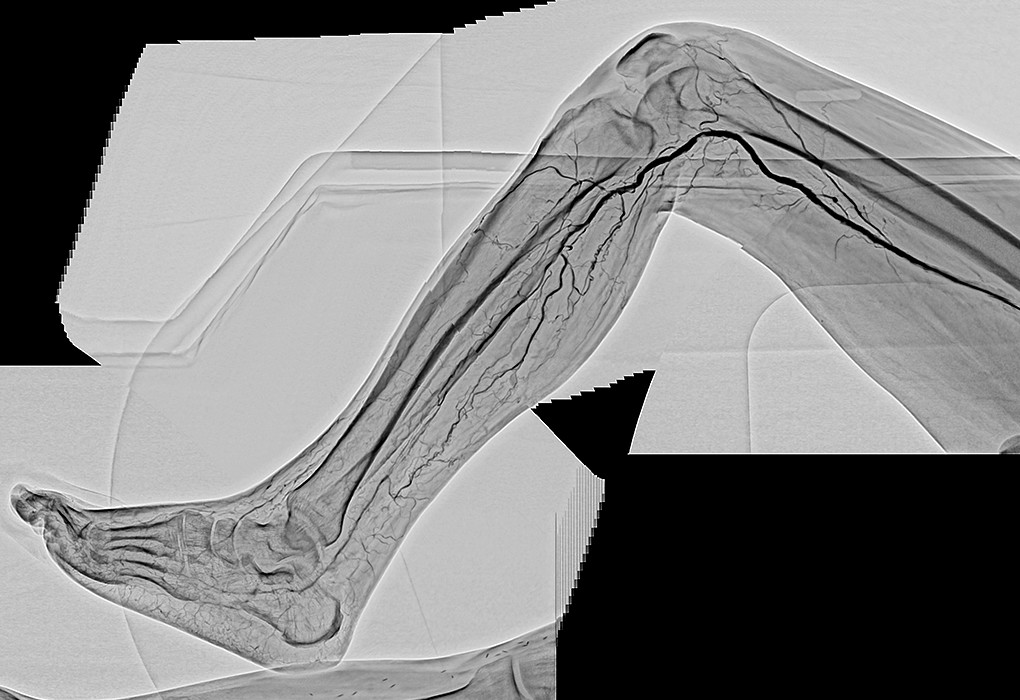

- 首先,双腿能拍到同一画面中这一点很好。还有手术中,由于能够区别使用纵向16英寸、横向16英寸,例如,希望拍摄双腿全长时可以横着跟踪拍摄。采用DSA时,由于迄今为止也都不得不分几次进行拍摄,因此需要患者承担造影剂的负担,而我认为拍摄次数减少对于患者来说是大有裨益的。但即便如此,如果不能拍摄冠状动脉就没有意义了,然而这台机器对于冠状动脉也可以正常拍摄。在搭桥等过程中,无需跟踪也可以将希望看到的区域全部拍摄出来,因此画面不会发生抖动,容易拍摄。

另外,正如曾我医生所说的那样,在跟踪拍摄时,通过将16英寸一侧置于横向,可以一次拍摄到双下肢的全部长度,导管床也在纵向的移动行程长,仅通过移动导管床就可以拍摄到足尖的位置。

- 是的。的确非常好。图像会随时自动抖动补偿,显示出没有失准的清晰的DSA,所以我都认为成是理所当然的事情了。丝毫没有不适感,感觉适合用于末梢血管的拍摄。